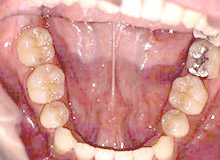

矯正治療前

矯正治療後(完成型)